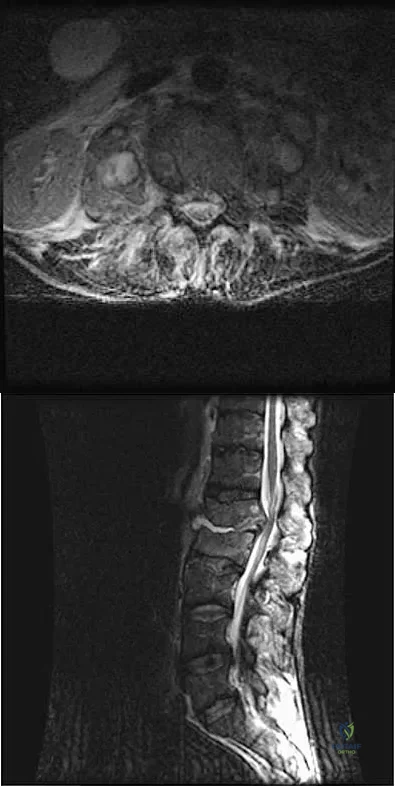

A 32-year-old man notes increasing back pain and progressive paraparesis over the past few weeks. He is febrile, and laboratory studies show a WBC of 12,500/mm3. MRI scans are shown in Figures 6a and 6b. Management should consist of

Explanation